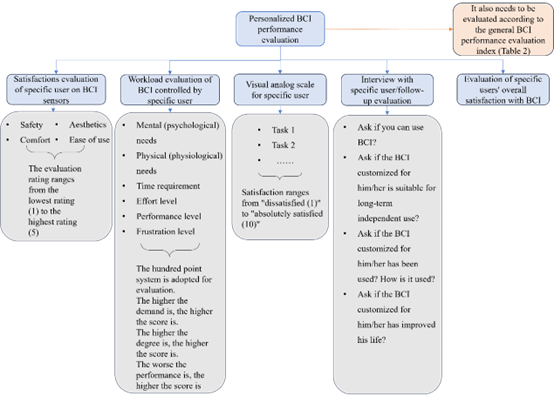

3 个性化BCI性能评价

为比较不同BCI系统的性能,报告其性能的准则至关重要[2],个性化BCI也不例外(如图2c所示)。此外,个性化BCI性能评价方法也方便特定用户对该类BCI进行评价以促进其完善。

个性化BCI是在通用BCI的基础上设计研发的(如图2b所示),因此,个性化BCI性能也需要按照通用BCI性能指标进行定量或客观的评价,除此而外,还需要从特定BCI用户的角度出发,通过满意度等指标对其进行评价[30,54]。

3.2 个性化BCI性能评价方法

在图4中,特定用户对BCI传感器的满意度评价极为重要,因为BCI传感器的性能会严重影响用户对BCI的接受度[30,54],特定用户操控BCI的工作负荷评价也会影响用户对BCI的接受度[30]。除此而外,也包含了特定用户的视觉模拟量表[2,58],以及特定用户对BCI总体满意度评价[30,54],后者可采用用户对辅助技术满意度评价表 Quest 2.0 及其扩展表[56,58,59]。特别需要注意的是,与特定用户面谈/随访评价非常必要和重,其中的四个问题是BCI技术转化为实际应用需要考虑的[1]。

图4个性化BCI性能评价方法